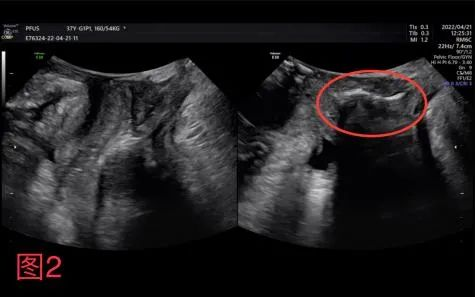

据悉,曾有一名37岁女性患者,因打喷嚏漏尿加重来诊。经盆底超声检查,发现患者不但有压力性尿失禁、膀胱膨出、肛门外括约肌局部损伤的超声表现,还伴有后腔室小肠疝出征象,明确了患者阴道脱垂的主要原因。临床检查不能对阴道脱垂从外部形态做出判断,而盆底超声可以对深部组织情况进行准确评估。盆底超声应用临床以来,充分显示了其优越性。

图2:小肠自阴道后壁与直肠间疝出(红色圈)